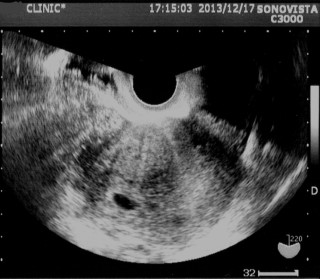

まだ袋だけしか見えませんが、この24日後の健診で、この袋の中に2つの心臓があり、一卵性の双子と分かりました♪

エコー写真

あなたのエコー写真と比べてみては...